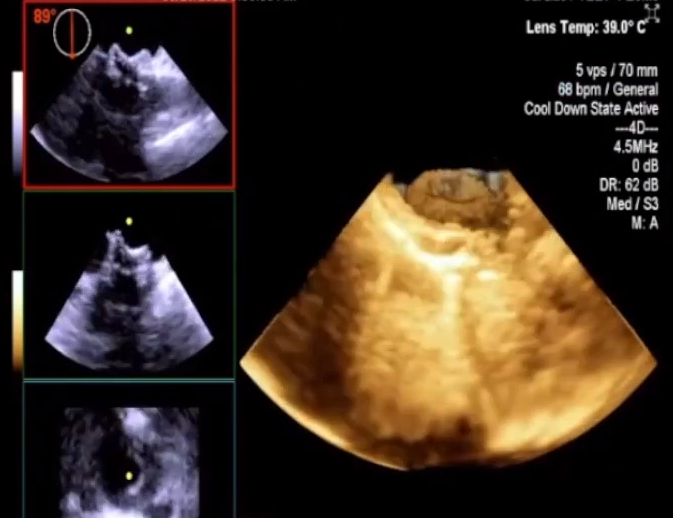

该患者是一名12岁男孩,近日在广州市妇女儿童医疗中心诊断为先天性心脏病,室间隔缺损(膜周型)。术前超声评估结果显示,室间隔缺损可见约6mm,CDFI提示室水平左向右分流,峰值流速4.1m/s,压差68mmHg。

▲术前超声

综合患儿家属意见,考虑到患儿术后获益最大化,经专家团队讨论后,拟使用我国自主研发的MemoSorb®全降解封堵器系统行室间隔缺损封堵术。手术在广东省人民医院张智伟教授的指导下,由广州妇女儿童医疗中心陈欣欣教授团队(心内科张旭、张丽、汪周平)顺利完成。

▲术后超声